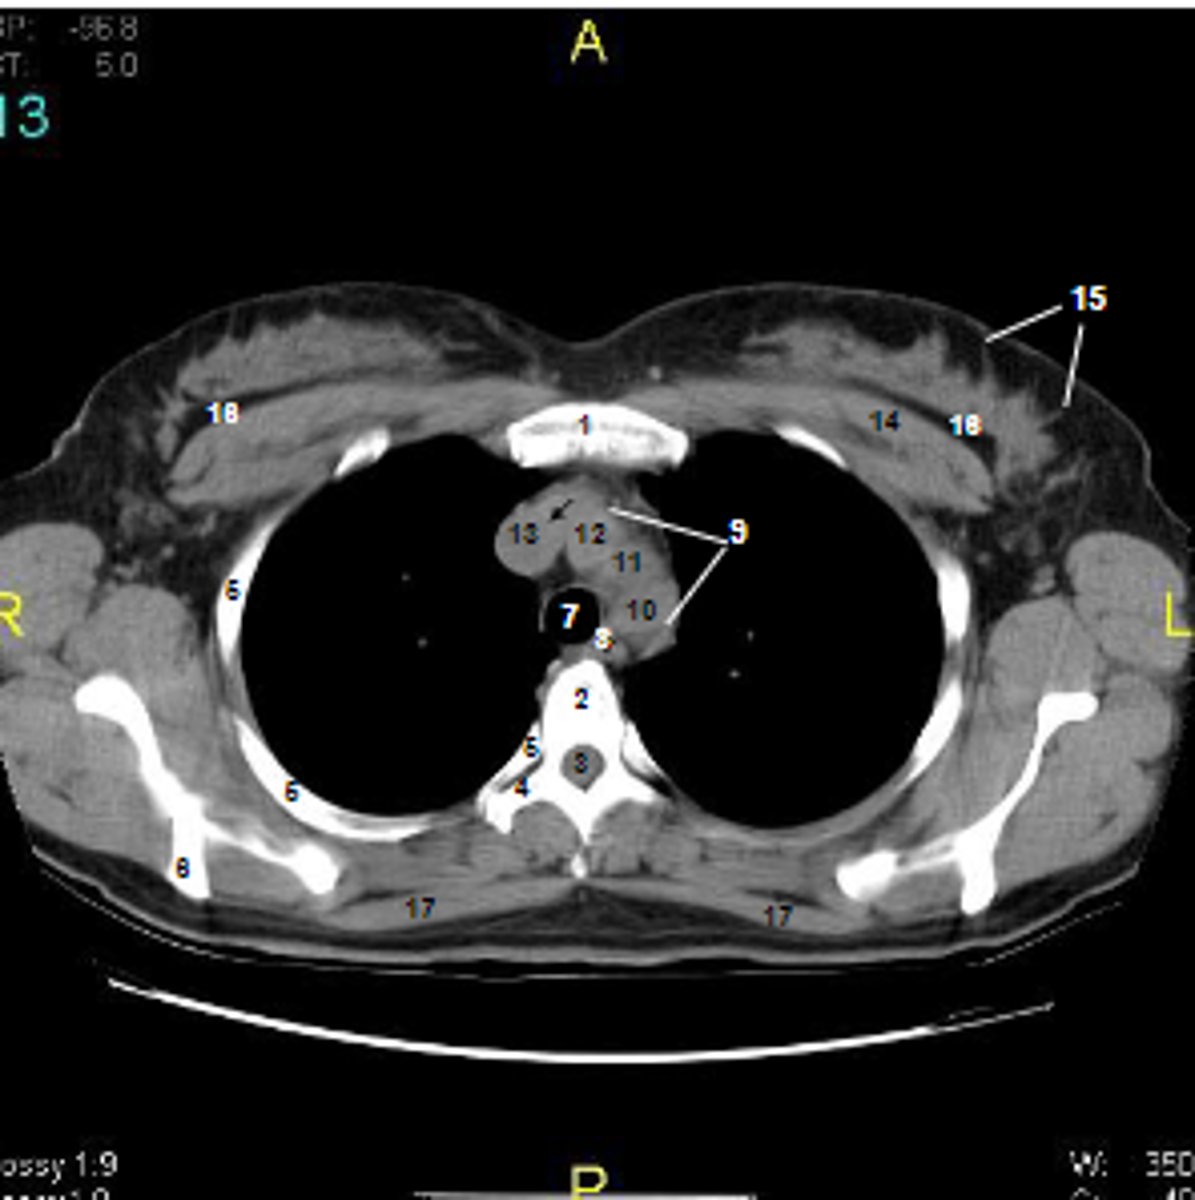

1

at what number is the sternum

2

at what number is the vertebral body

3

at what number is the vertebral canal/ spinal cord

4

at what number is the transverse process of vertebra

5

at what number is the rib

6

at what number is the spine of scapula

7

at what number is the trachea

8

at what number is the esophagus

9

at what number is the arch of aorta

10

at what number is the left subclavian artery

11

at what number is the common carotid artery

12

at what number is the brachiocephalic trunk

13

at what number is the superior vena cava

14

at what number is pectoralis major

15

at what number are Cooper's ligaments

16

at what number is the retromammary space

17

at what number is trapezius